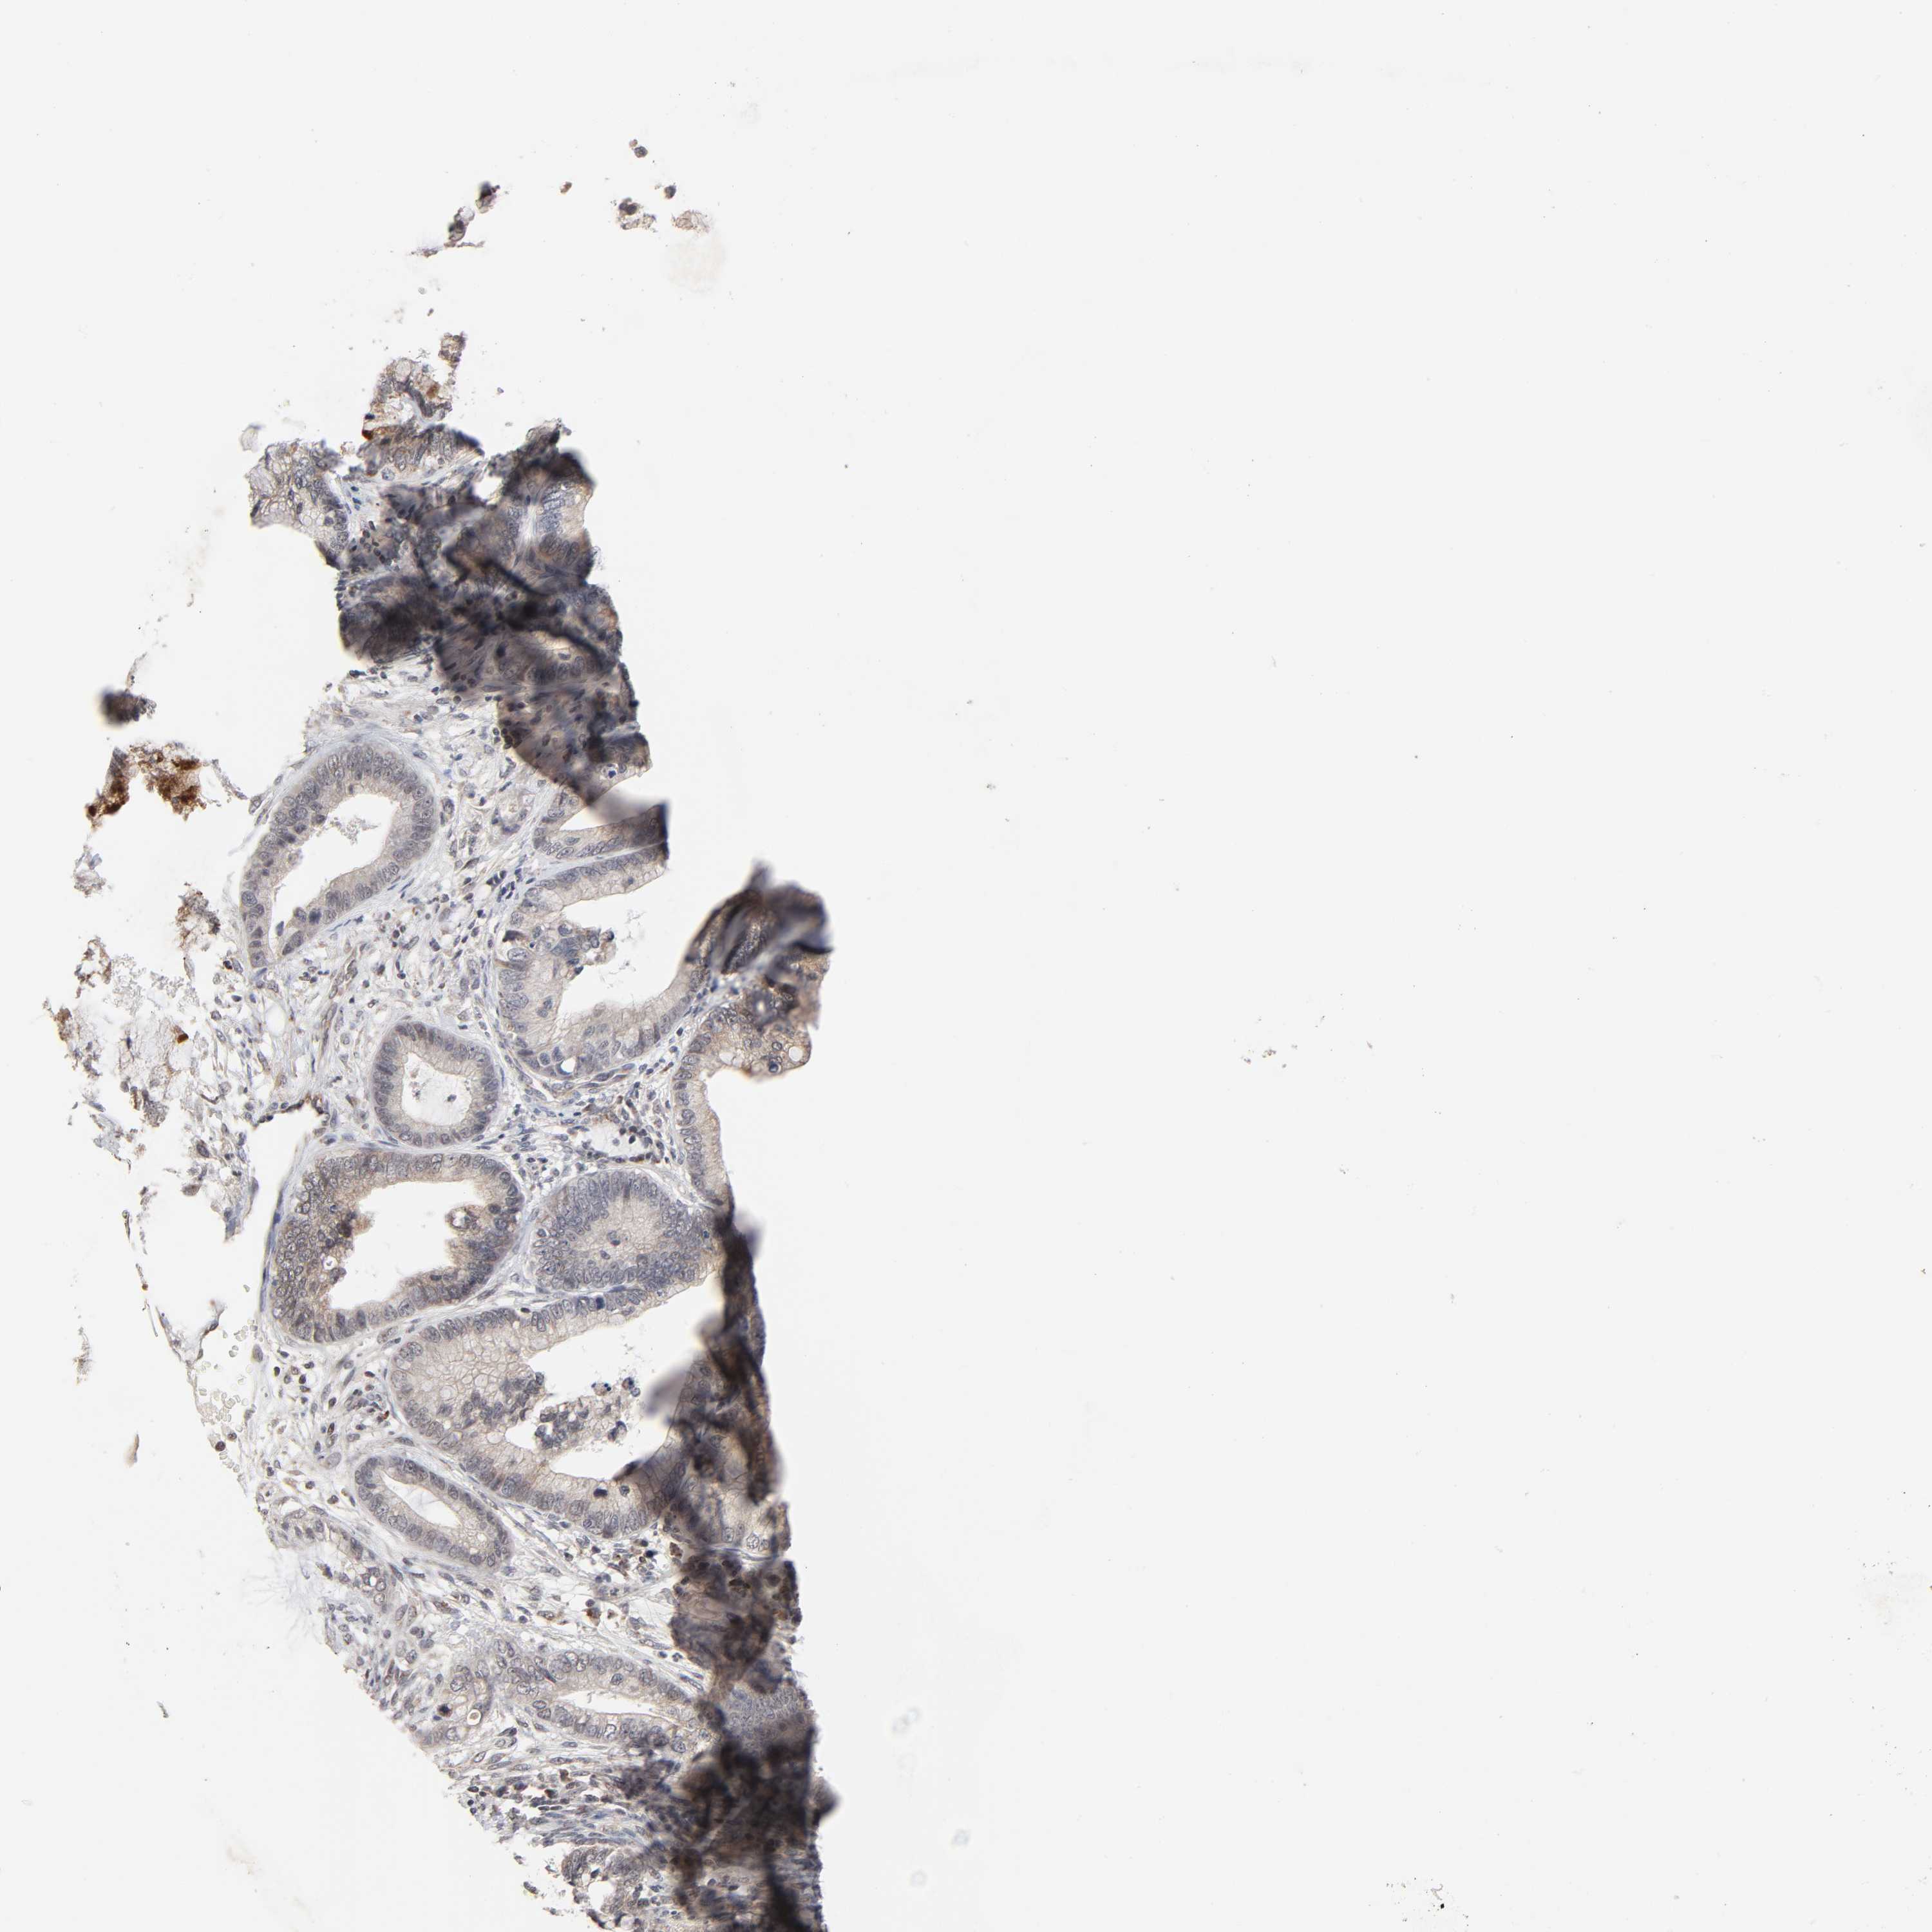

CERVICAL CANCER - Protein expressioni

A mouse-over function shows sample information and annotation data. Click on an image to view it in a full screen mode. Samples can be filtered based on level of antibody staining by selecting one or several of the following categories: high, medium, low and not detected. The assay and annotation is described here.

Note that samples used for immunohistochemistry by the Human Protein Atlas do not correspond to samples in the TCGA dataset.

Antibody stainingi

Antibody staining in the annotated cell types in the current human tissue is reported as not detected, low, medium, or high, based on conventional immunohistochemistry profiling in selected tissues. This score is based on the combination of the staining intensity and fraction of stained cells.

Each image is clickable and will lead to virtual microscopy that enables deeper exploration of all samples and also displays staining intensity scores, fraction scores and subcellular localization as well as patient and tissue information for each sample.

Antibody HPA004171

Staining

High

Medium

Low

Not detected

Intensity

Strong

Moderate

Weak

Negative

Quantity

>75%

75%-25%

<25%

None

Location

Nuclear

Cytoplasmic/membranous

Cytoplasmic/membranous,nuclear

Squamous cell carcinoma, NOS

Adenocarcinoma, NOS